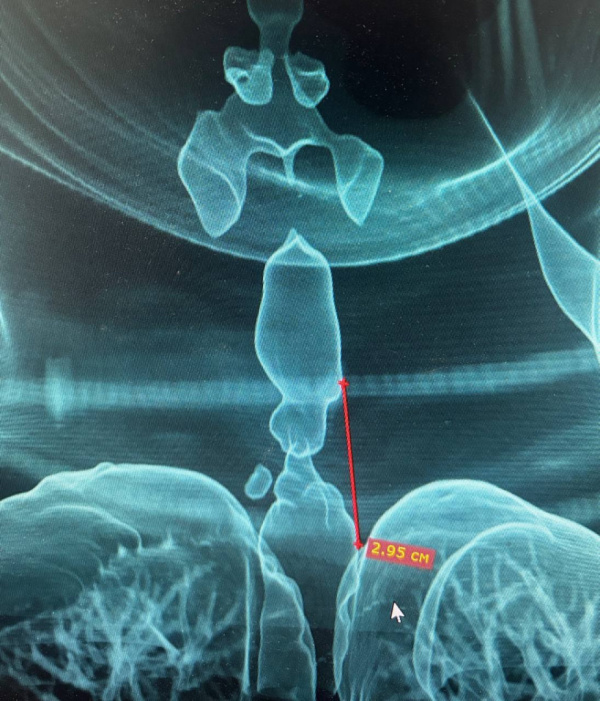

Со временем у пациентки развилась выраженная одышка и характерный шум при дыхании. Для диагностики медики провели бронхоскопию и компьютерную томографию шеи и грудной клетки. Обследование выявило рубцовое сужение — стеноз трахеи.

Чтобы точно оценить протяжённость и расположение сужения, специалисты ГКБ №9 создали 3D-модель дыхательных путей. Протяжённость стеноза составила 2,95 см, а минимальный просвет трахеи сузился до 5 мм, что создавало прямую угрозу жизни.